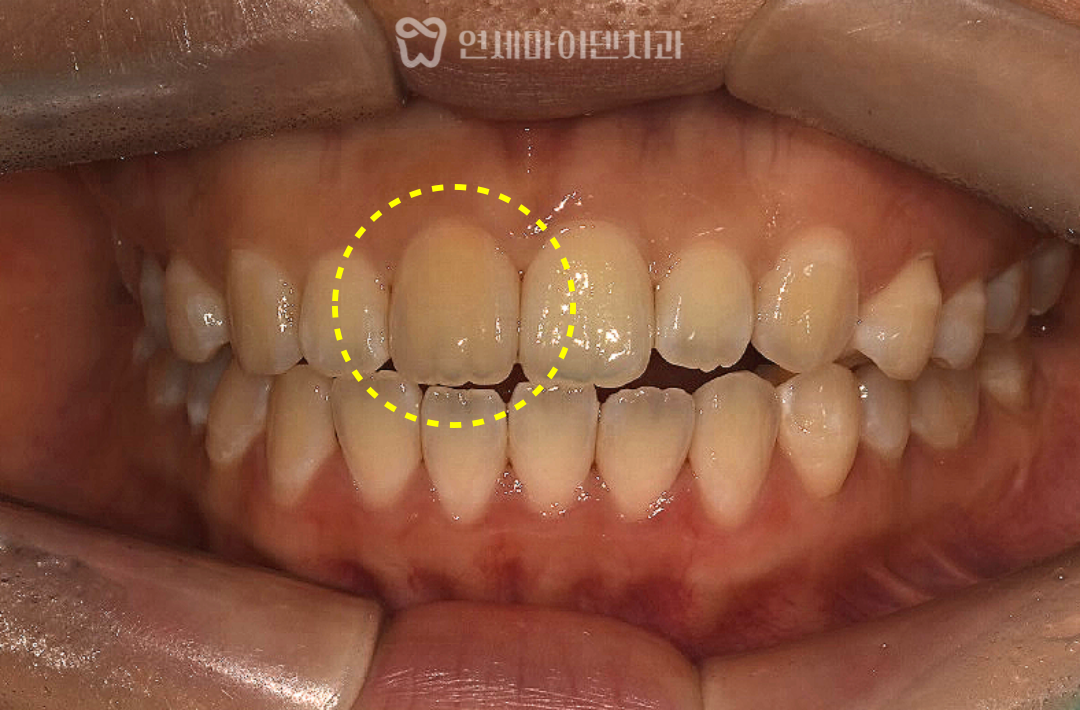

정상 치아와 비교해 보았을 때

해당 치아만 유독 어둡고 노란빛을 띤다면

표면 문제가 아니라

치아 내부 변화 가능성을 우선적으로

생각해볼 수 있습니다.